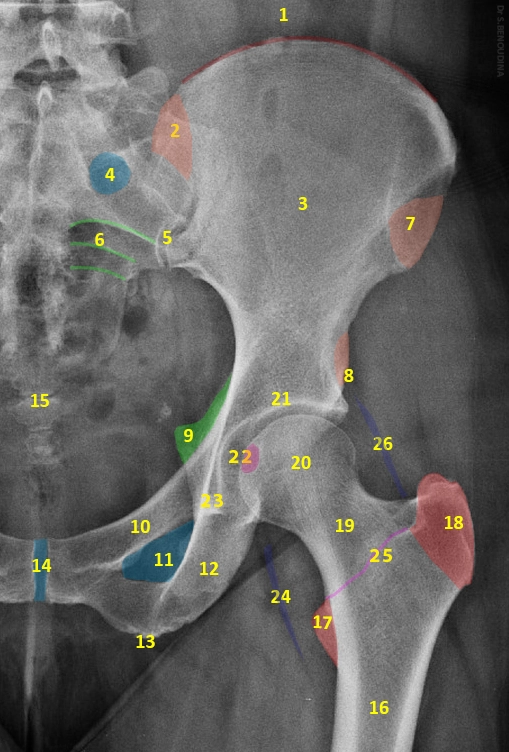

X Quang khớp háng

16/03/2026